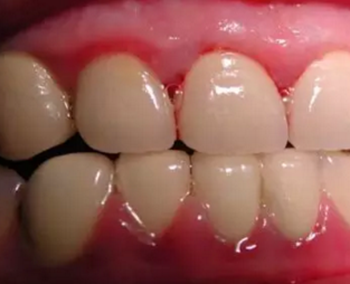

這種情況下,建議大家及時接受醫(yī)生的專業(yè)治療(如洗牙),去除對牙齦的刺激。因為一旦牙齦處于炎癥狀態(tài),必須及早治療才有可能恢復到健康狀態(tài),明顯減少出血甚至不出血。

一旦病情發(fā)展,引起牙齒周圍牙槽骨的吸收,這種破壞將是不可逆的,治療也復雜得多。